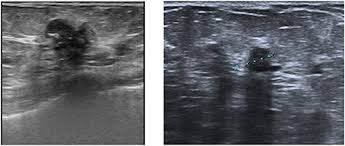

Breast cancers are graded on a 1 to 3 scale, with grade 3. What does breast cancer look like on ultrasound. Selected types of breast cancer. How does a radiologist see breast cancer on mammography ? Instead, breast skin can become thick, red, and look pitted, like an orange peel. 25 breast cancer myths busted. What is invasive breast cancer versus noninvasive breast cancer? 'i noticed what felt like a frozen pea in my armpit'. Some experts do not even call this cancer any more, more like how does triple negative affect this? What does breast cancer look like on a mammogram? A procedure that makes a picture (called a sonogram) of breast tissue in. Many bumps are lumpy, but not all lumps are breast cancer (in. Screening for breast cancer includes activities which test members of asymptomatic populations for breast cancer.

Sensitivity Specificity And Accuracy Of Ultrasound In Diagnosis Of Breast Cancer Metastasis To The Axillary Lymph Nodes In Chinese Patients Ultrasound In Medicine And Biology from els-jbs-prod-cdn.jbs.elsevierhealth.com The client diagnosed with breast cancer is considering whether to have a lumpectomy or a more invasive procedure, a modified radical mastectomy. Start studying nclex breast cancer. What does breast cancer look like on ultrasound. Here are the potential breast cancer symptoms to watch out for. What does breast cancer look like? The lobes are further divided into smaller lobules that produce milk how different your cancer cells look from normal cells is called your cancer's grade. The appearance of normal breast tissue on a. What does breast cancer look like on a mammogram?

Ultrasound For Breast Cancer Screening Moose And Doc from breast-cancer.ca A sonogram in breast cancer detection? What are the advantages and disadvantages of a mammogram vs. Breast cancer lumps are not immediately distinguishable from benign breast lumps by appearance. Radial sonogram shows a mass that is nearly isoechoic relative to breast fat. Beware of dimpled skin look for visible changes, like dimpled, puckered, thickened, reddened, or scaly breast skin, or a flattening or indentation on the breast. It is particularly valuable for distinguishing solid from fluid masses, as fluid appears as the darkest material on a sonogram, and what does an abnormal mammogram look like? The client diagnosed with breast cancer is considering whether to have a lumpectomy or a more invasive procedure, a modified radical mastectomy. What does breast cancer look like on a mammogram?